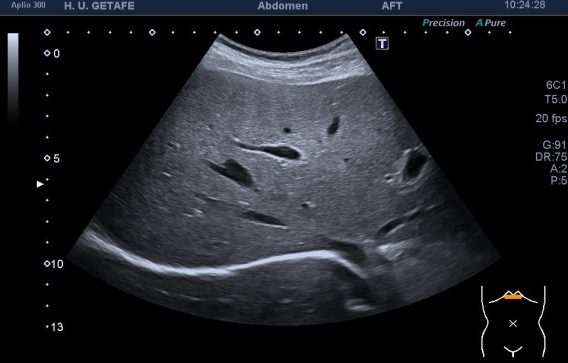

De la imagen 1 a 3 ves un hígado afectado por una cirrosis hepática. En ella vas a ver un tejido anormalmente heterogéneo, parcheado en ocasiones, como con «grumos», a veces muy pequeños, otras veces más grandes. Son los nódulos de regeneración. Cuando las células del tejido hepático se mueren son sustituidas por tejido cicatricial. Puedes ver el borde hepático abombado. Los cambios en la ecogenicidad son variados, te he decimos algunos, no me interesa contarte esto, me interesa que compares la imagen 1,2 y 3 con la imagen 4 y veas patología y normalidad del parénquima hepático. Muchas veces una imagen vale más que mil palabras, lo sé…